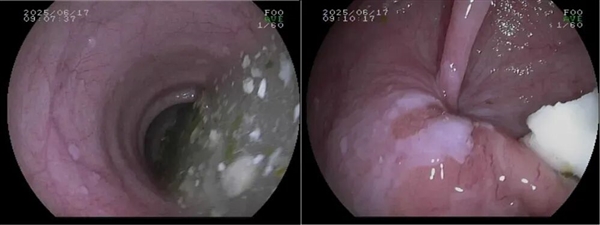

3、胃镜检查

诊断贲门失弛缓症和排除肿瘤的“侦察兵”,食管可能明显变粗(扩张),严重时像被撑大的水管,甚至出现弯曲扭曲,不像正常食管那样笔直通畅。其次,扩张的食管里常残留食物残渣和黏液,黏膜被长期浸泡得发红水肿。

最关键的是贲门,医生把胃镜往胃里送时,会明显感觉这里阻力很大,像推一扇锈死的门——正常贲门碰到胃镜会自然放松,这里却僵着,得突破阻力才能慢慢通过。

不过和肿瘤不同,贲门和食管的黏膜表面一般没有溃疡、肿块这些异常凸起,主要问题是“门打不开”和“通道变形”,不是“长了坏东西”。

胃镜:食管扭曲扩张、食物残渣和黏液潴留,贲门紧闭,胃镜通过阻力明显。